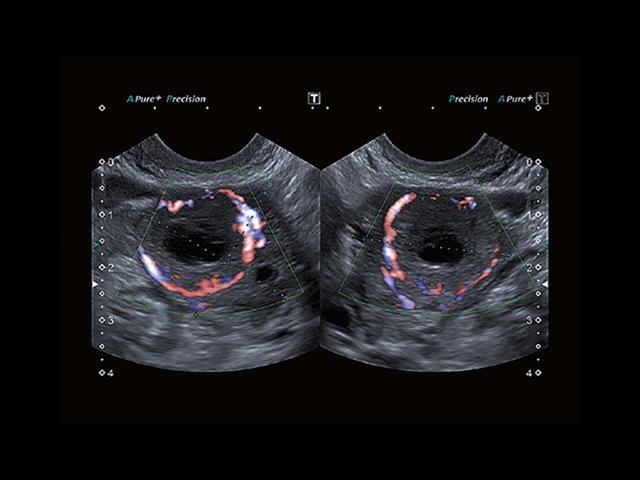

Обновленная версия легендарного УЗ-сканера. Стационарный аппарат экспертного класса Aplio 500 Toshiba NEW, визуализирует анатомические структуры в высоком разрешении. Модель позволяет выявить микрокальцификаты, новообразования, нарушения в работе сердца, сосудов и мышц. Присутствует функция виртуальной эндоскопии, 4D-сканирования, эластометрии тканей, УЗИ с контрастированием. За повышение качества изображения отвечают технологии ApliPure и Superb Microvascular Imaging. Первая задействует возможности пространственного и частотного кодирования, формирует цельный визуальный ряд с сохранением клинических маркеров. Вторая улучшает отображение микрососудистого русла, используя доплеровский эффект. Модель оснащена 21-дюймовым монитором, имеет 4 активных порта. Возможно подключение педиатрических, интраоперационных, лапароскопических и чреспищеводных датчиков.

- SMI. Опция, упрощающая визуализацию микроциркуляторного русла. С ее помощью обследуются сосуды с низкой интенсивностью кровотока, изучаются наиболее тонкие структуры. SMI упрощает диагностику новообразований, минимизирует вероятность ошибки.